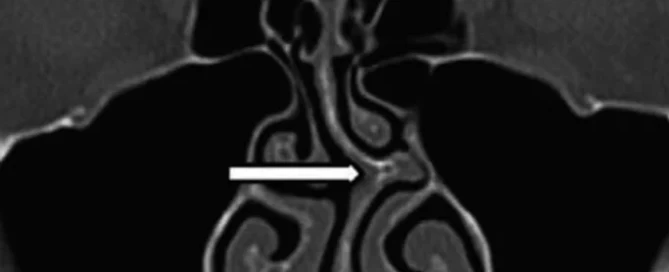

Els cornets són unes estructures carnoses que es troben al nas i que tenen la funció de regular el flux aeri nasal així com modificar les condicions d'humitat i temperatura de l'aire que respirem. Són dues estructures cilíndriques que, mitjançant un sistema vascular, s'omplen i es buiden de sang segons cada moment. Per exemple, en